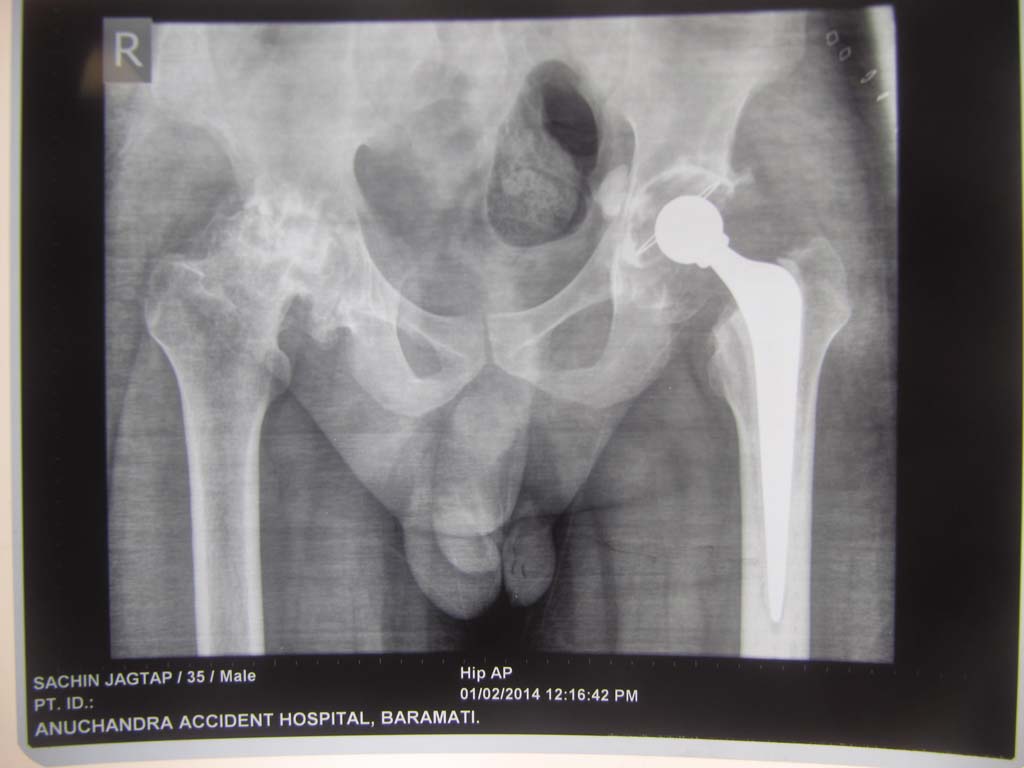

We provide all type of joint care and joint replacement services

All types of Associated services like X-ray, I.C.U, etc are available with Us

Recent cases

We have done many major and minor surgeries in my hospital in last 14 years including trauma/spine/joint replacements etc.